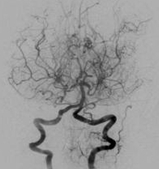

이름에서 유추할 수 있듯이 일본에서 처음 만들어진 용어로서 일본의 스즈키 교수에 의해 명명된 특수한 뇌혈관질환입니다. 뇌동맥 조영상이 아지랑이처럼 흐물흐물해서 뿌연 담배연기 모양을 뜻하는 일본말인 모야모야라고 명명되었다고 합니다.